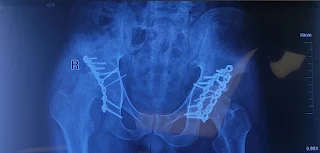

Our patient was a 30-year-old male with painful AVN of the femoral head, years after an acetabular fracture that had been treated with ORIF and a posterior wall reconstruction plate. He had a pre-existing foot drop.

We performed a metal-on-poly Total Hip Replacement (THR) via the posterior approach to reduce the patient cost. The plan was to retain the posterior plate, but as is often the case, bones have their own plans. The plate obstructed the optimal placement of the acetabular cup, so we had to remove it.

3. THA in patients with prior acetabular ORIF

A paper by our mentor himself and the team, has highlighted the following:

“Previous implants if any should be removed only if they are in the way of cup implantation or infected.5 Press fit uncemented modern porous metal acetabular component with multiple screw options is the preferred implant for the majority of cases. Complex fractures may require major reconstruction with revision THA implants especially when a pelvic discontinuity is present.“

Besides, the posterior capsule and external rotators are often fibrosed and distorted and the acetabular socket may not be hemispherical anymore posing further challenges.